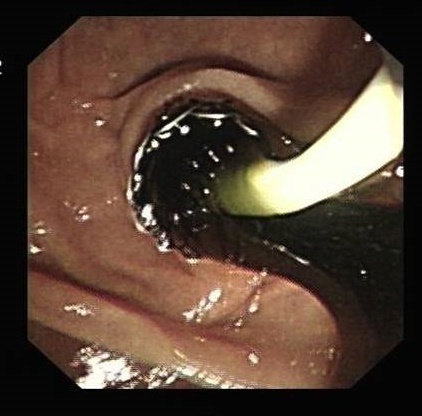

取石网篮取石 取石球囊取石